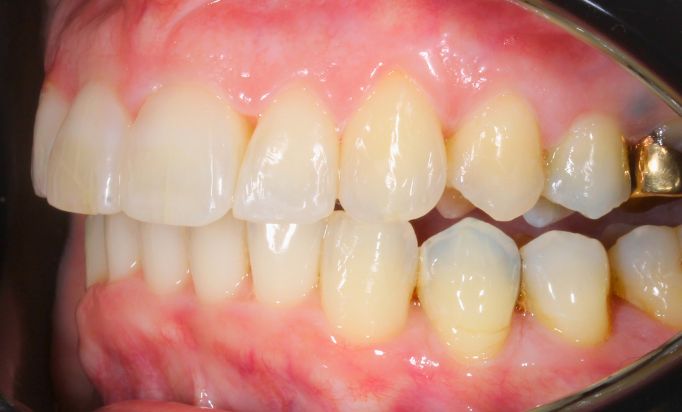

Invisalign®

Aligned teeth, confident smiles

Achieve stunning teeth alignment without the metal brackets.